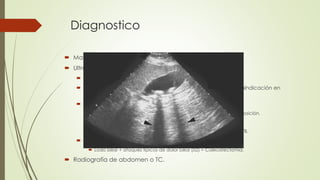

Diagnostico

 Manifestaciones típicas e imagenología.

 Ultrasonido abdominal.

 Estándar diagnostico (Sensibilidad y especificidad >90%)

 No invasivo, no doloroso, sin exposición a radiación, sin contraindicación en

pacientes críticos.

 Hallazgos en colecistitis crónica.

 Hiperecoico con sombra acústica. Movimiento con cambios en posición.

 VB de menor tamaño, pared gruesa.

 VB agrandada con pared delgada  obstrucción del cuello de VB.

 Manifestaciones típicas sin evidencia de cálculos.

 Lodo biliar + ataques típicos de dolor biliar (≥2) = Colecistectomía.

 Radiografía de abdomen o TC.